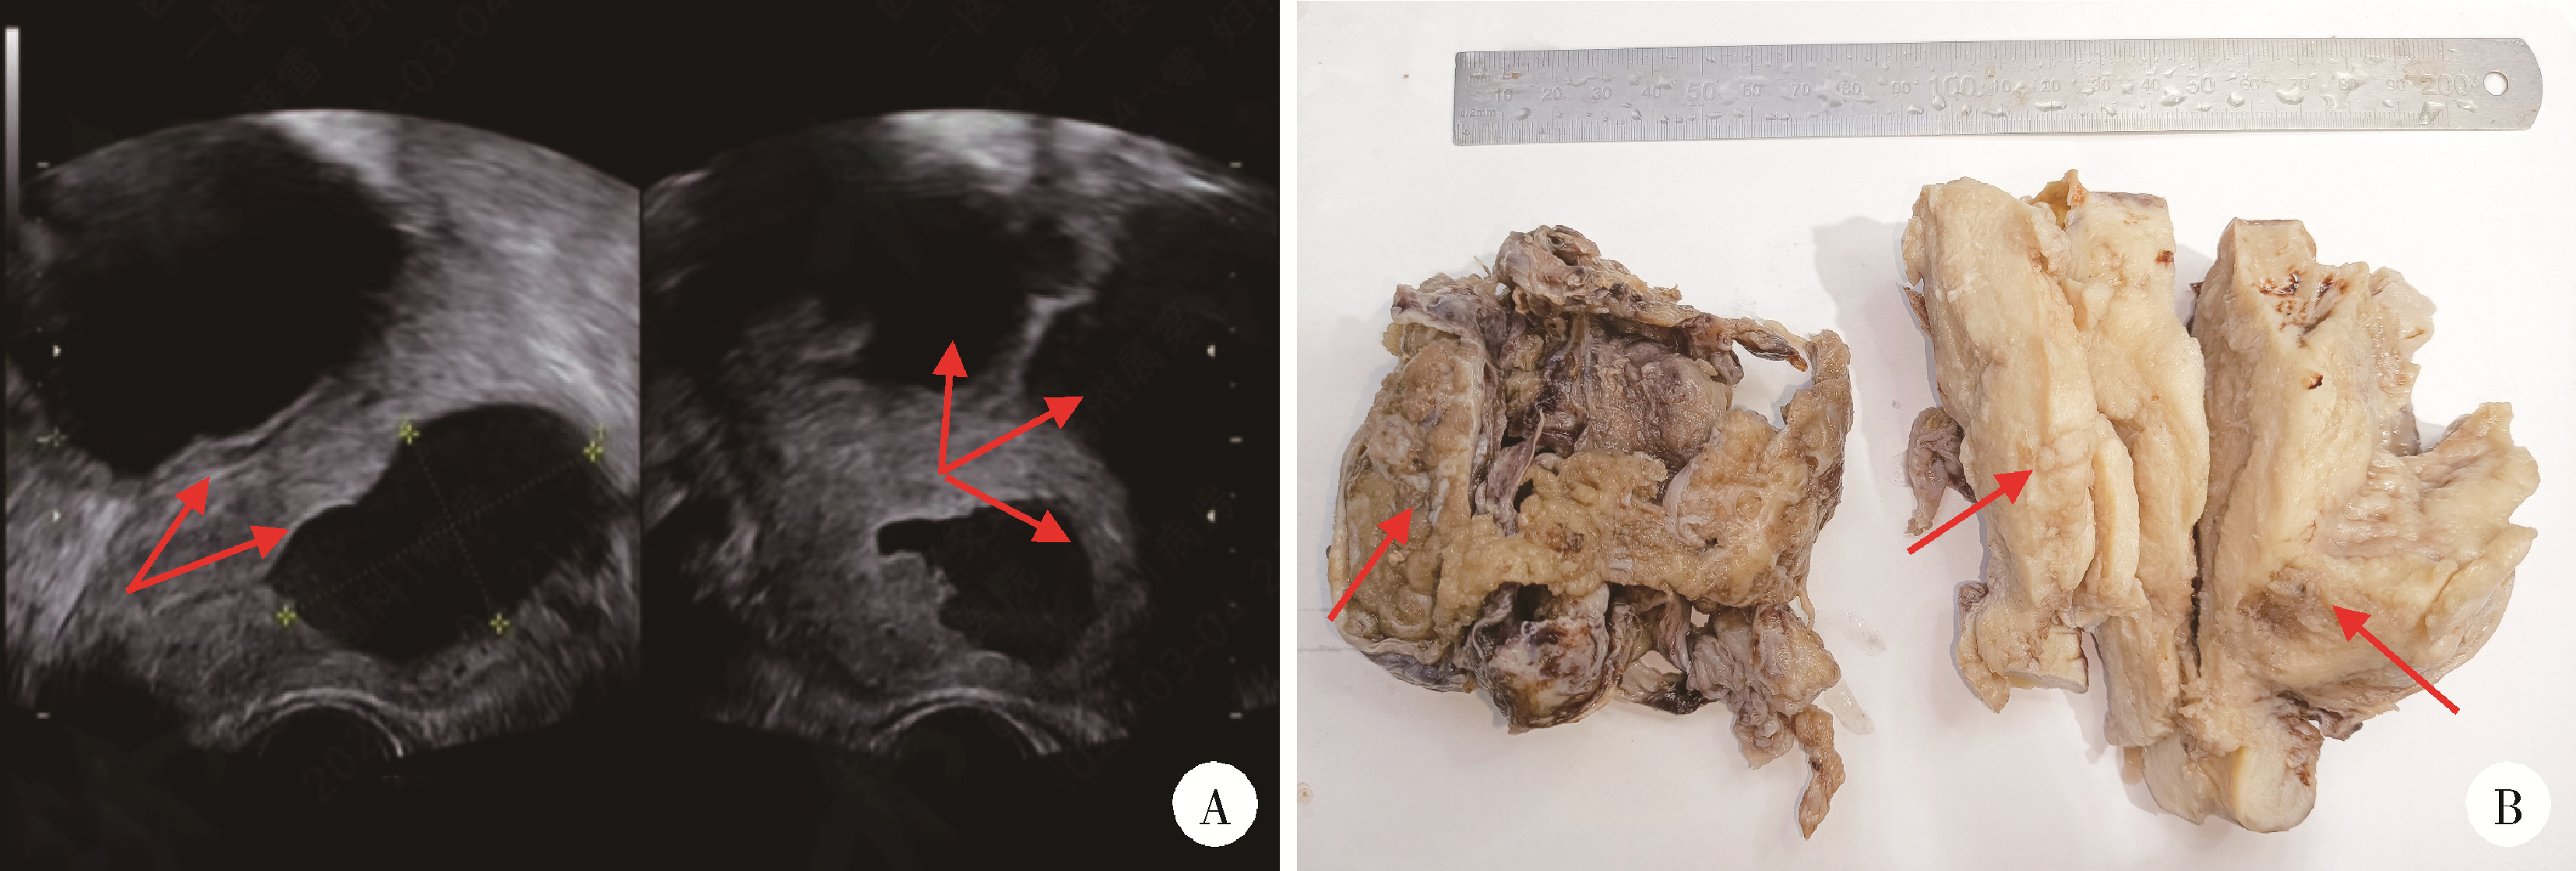

Xiaolin WANG1, Luyao LI1, Wen ZHANG2, Hongyan WANG1,*(